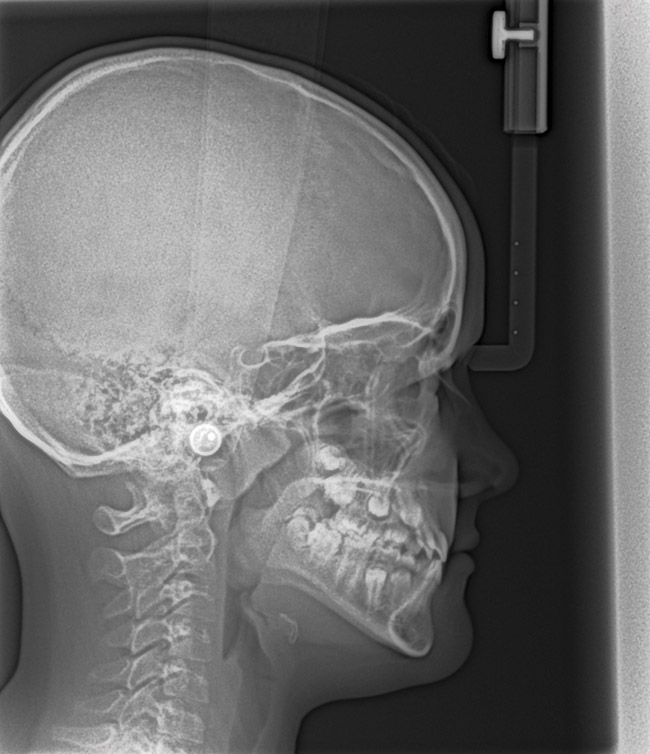

(15.) Cephalometric evaluation demonstrates significant tonsillar blockage of the airway and bimaxillary retursion.

Figure 15

(21.) Six-year-old male presents nocturnal bruxism, habitual snoring, and behavioral issues. PSG reports an AHI of 9.6/hr and respiratory effort–related arousal (RERA) of 14.2/hr (Case provided by Kathy French, DDS).

Figure 21

(22.) Radiograph highlights the obstructed nasal airway preoperatively. Three months after T&A, another PSG demonstrated an AHI of 0.3 and RERA of 0.0/hr.

Figure 22